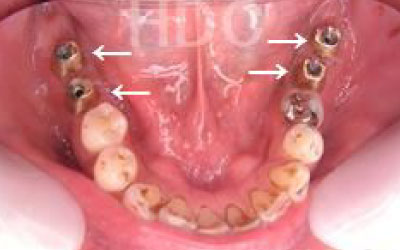

1人の歯科医師の視点でなく、複数のドクターでCTの診断や計画を立てています。

CTを使うと、骨や歯の状態を立体的に確認でき、正確な距離も測定できます。

骨の厚さや傾き、神経の位置などを事前に詳しく把握することで、安全にインプラント治療を行うことができるのです。

2 神経を傷つけるリスク

顎の骨の中には神経が通っており、インプラント治療の際にそれを傷つけてしまうリスクがあります。

しかし、当院では事前にCT撮影を行い、神経までの距離を三次元的に正確に把握した上で治療計画を立てるため、リスクをしっかり回避できます。

さらに、骨を削りすぎないようにするための専用のストッパーも導入しており、安全性には十分に配慮しています。